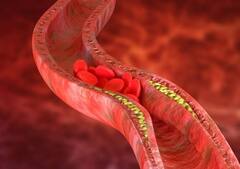

Heartburn in Pregnancy: प्रेग्नेंसी में इन कारणों से हो सकती है हार्टबर्न की समस्या, इस तरह पाएं छुटकारा

प्रेग्नेंसी के दौरान महिलाओं को कई तरह की समस्याओं का सामना करना पड़ता है. इन्हीं समस्याओं में पेट में गैस, बदहजमी, अपच, कब्ज जैसी परेशानी शामिल है. यह सभी समस्याएं शरीर में हो रहे हार्मोनल बदलाव की वजह से होती है. दरअसल, गर्भावस्था के दौरान पेट में मौजूद एसिड फूड पाइप के जरिए वापस आता है. ऐसे में जलन की परेशानी गले और सीने में पहुंचने लगती है. इस परेशानी से राहत पाने के लिए आप कुछ घरेलू टिप्स फॉलो कर सकती हैं. आइए जानते हैं इन घरेलू टिप्स के बारे में- (Photo - Pixabay)